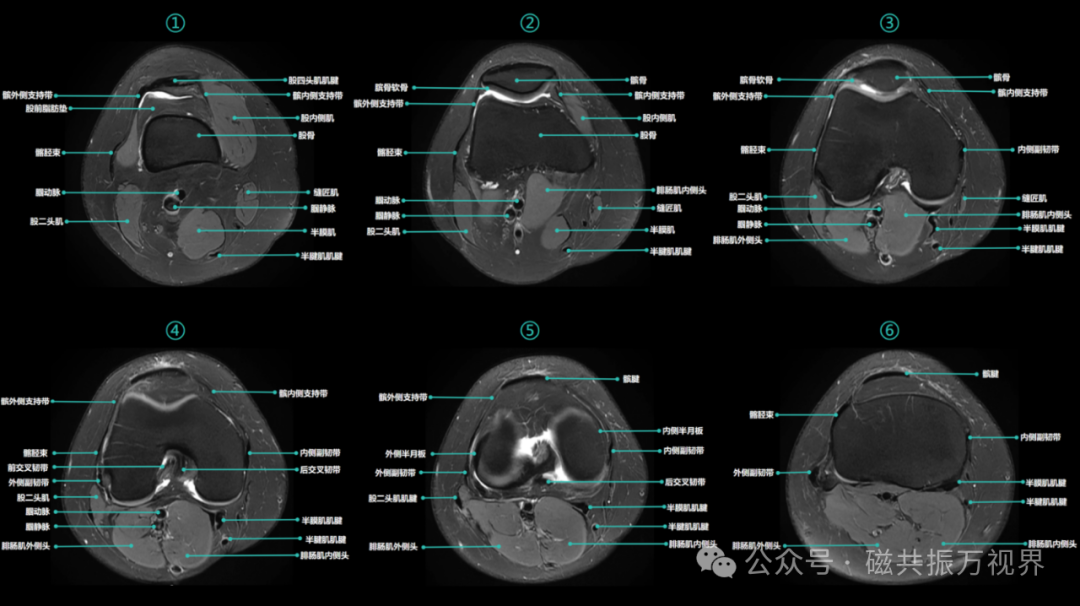

1)轴位(自上而下)

膝关节构成肌肉:股内侧肌、股外侧肌、股四头肌、股二头肌、缝匠肌、半膜肌、半腱肌、腓肠肌、比目鱼肌、股中间肌等。